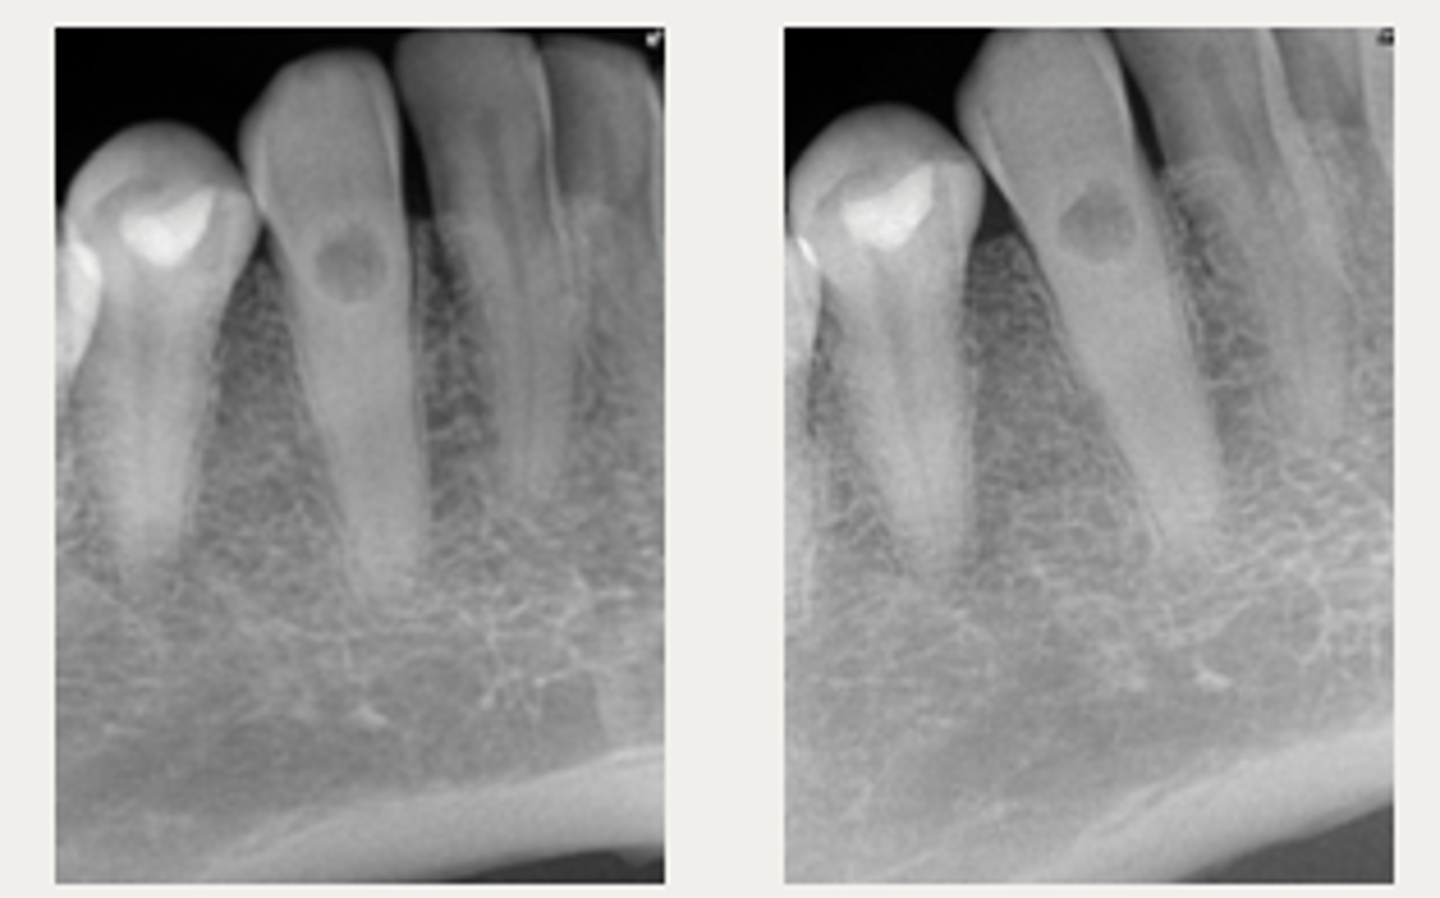

External cervical resorption (Invasive Cervical Resorption)

ID the type of resorption:

- Usually an incidental radiographic finding, especially for less advanced lesions

- Variable appearances; may be a well-defined or irregular radiolucency around the cervical aspect of the tooth

- A portal of entry is always present in the cervical region of the tooth

- The chamber/canal outline is often visible as the innermost layer of predentin around the chamber is not resorbed

Patient presents with these radiographic findings, what type of resorption?

- Incidental finding

- Radiolucency around cervical aspect of tooth

- Portal of entry present in cervical region

- Chamber/canal outline is visible

What type of lesion is similar to internal resorption but is distinguished by taking an off-angle PA in which the lesion moves?

Internal inflammatory resorption

If you take an off-angle PA and the lesion does NOT move, what do you suspect?